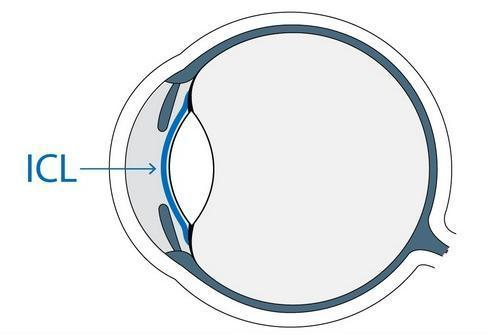

那麽,像小美這種角膜薄的,還有沒有辦法恢複視力?答案就是(shì)——ICL晶體植入術。

如果說激光手術是(shì)使角膜變平變薄,類似于“減法”,那麽,ICL晶體植入術就是(shì)在眼睛植入一塊比頭發絲直徑還薄的“超級隐形眼鏡”,類似于“加法”。“減法”時需要切削角膜,“加法”時無需切削角膜,自然對角膜厚度沒有要求。

在手術安全方面,ICL晶體植入是(shì)近視手術術式,在全球超過70多個國家廣泛應用。當然,ICL晶體植入不僅僅适用于是(shì)小美這樣的角膜薄患者,高度近視、幹眼症者以及所有青睐ICL術式的患者皆可以考慮。能否開展以完整的術前檢查結果爲準。